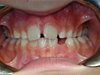

Cas 4

Enfant de 7 ans avec une étroitesse de la mâchoire supérieure et un décalage des milieux incisifs. Avec un quad-hélix, l'occlusion inversée du côté gauche s'est corrigée et les milieux se sont recentrés.